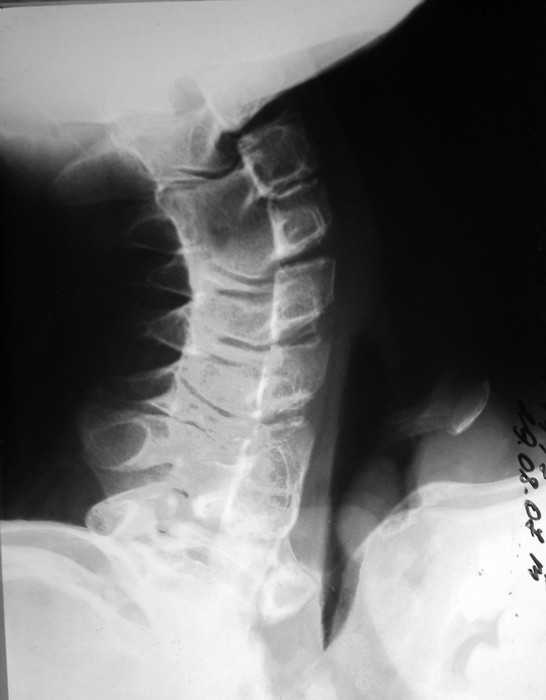

Re: Врожденная аномалия, множественные экзостозы

рентгенограммы